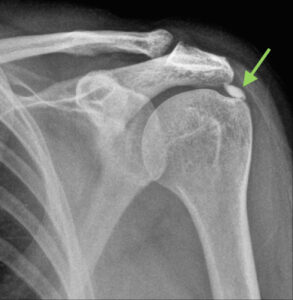

Het betreft een afzetting van calciumkristallen in één of meerdere pezen van de rotator-cuff. Deze kalkafzetting is eerder zacht (zoals tandpasta) en ziet er wit uit op radiografie. De rotator cuff is de meest aangetaste pees waar kalk zich neerzet. Niet iedereen met kalkafzetting in de schouder is zich daar bewust van of ervaart klachten.

Kalkdepot in de schouderpees

• Een röntgenfoto toont duidelijk de grote verkalkingen.

Calcificerende tendinitis van de schouder

Beeldvorming van peesverkalking in de schouder